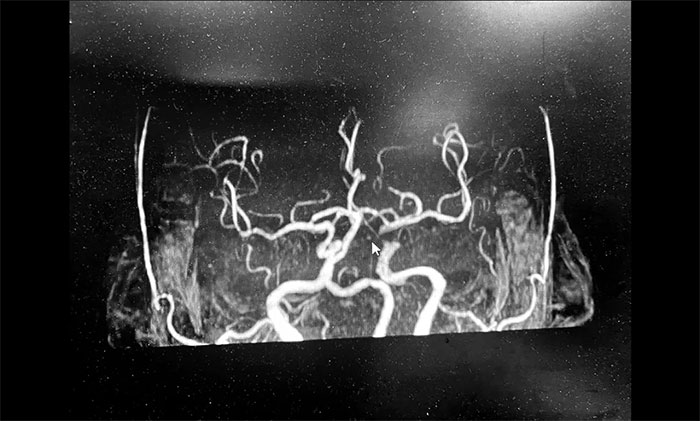

神經(jīng)內科3A病區(qū)周君主任詳細了解病史,查體,并為韓老伯完善相關的檢查。頭顱MRI示:腦干及雙側大腦半球多發(fā)陳舊梗死灶,左側胼胝體、半卵圓中心、側腦室旁及額葉多發(fā)梗死灶,偏亞急性期。腦動脈硬化,顱底動脈多發(fā)不同程度狹窄(左側頸內虹吸段為著)。

▲ 頭顱MRI示:左側多發(fā)梗死灶,左側頸內動脈狹窄

周君主任表示,從影像學上,患者左側腦室旁散在多個新鮮梗死灶,呈比較典型的“分水嶺樣梗塞”表現(xiàn)。分水嶺樣梗塞(Watershed infarction,WI),是指發(fā)生在腦部兩條主要動脈分布區(qū)的交界處的腦梗死,多發(fā)生于腦部較大動脈供血交界區(qū)。

韓老伯的新發(fā)病灶處在左側頸動脈供血支配范圍內,符合因左側頸內動脈狹窄而造成腦組織缺血表現(xiàn),需要針對這一引起腦梗的病因,及時采取干預治療措施。